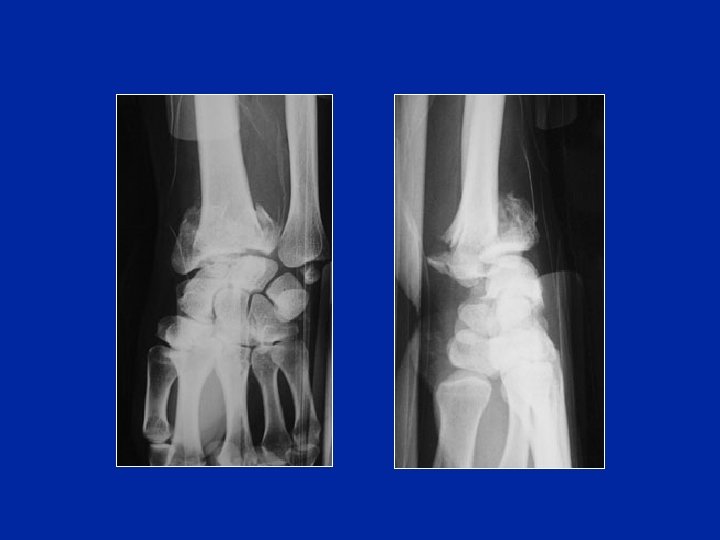

Fractures articulaires

Classification des fractures de l’extrémité inférieure du radius